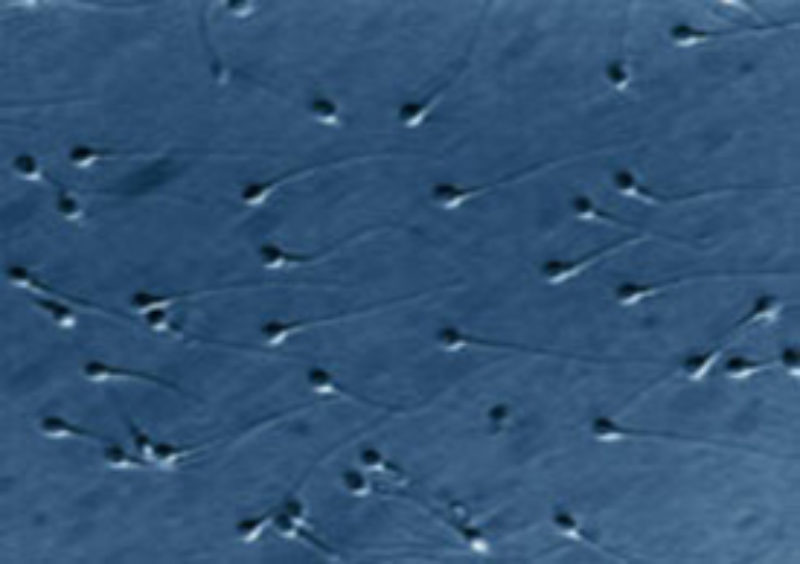

El estudio dinámico del ADN del semen aumenta el éxito de los tratamientos

CREA es uno de los primeros centros de medicina reproductiva que estudia la integridad de la molécula del ADN de los espermatozoides mediante esta novedosa prueba